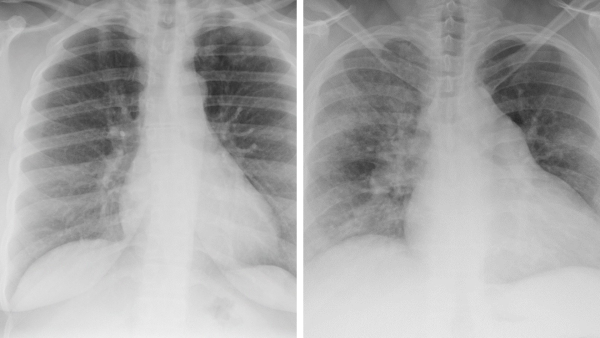

(Left) How large twists appear on a chest x-ray; (right) how small braids, starting with cornrows on the scalp, present on a chest x-ray.

That’s why their research is focused on educating radiologists—and Emergency Department physicians, too—about how Black hairstyles appear on scans. “We started by identifying the five popular Black hairstyles: small braids, large braids, small twists, large twists, and locs,” Udongwo says.

She and Dr. Maresky then created a board with examples of each style, and prepared slides to show what they look like on different types of imaging. “We wanted to be able to tell radiologists, ‘This is how a certain style appears on a radiograph, a chest x-ray, and a CT slice,’” Udongwo explains.